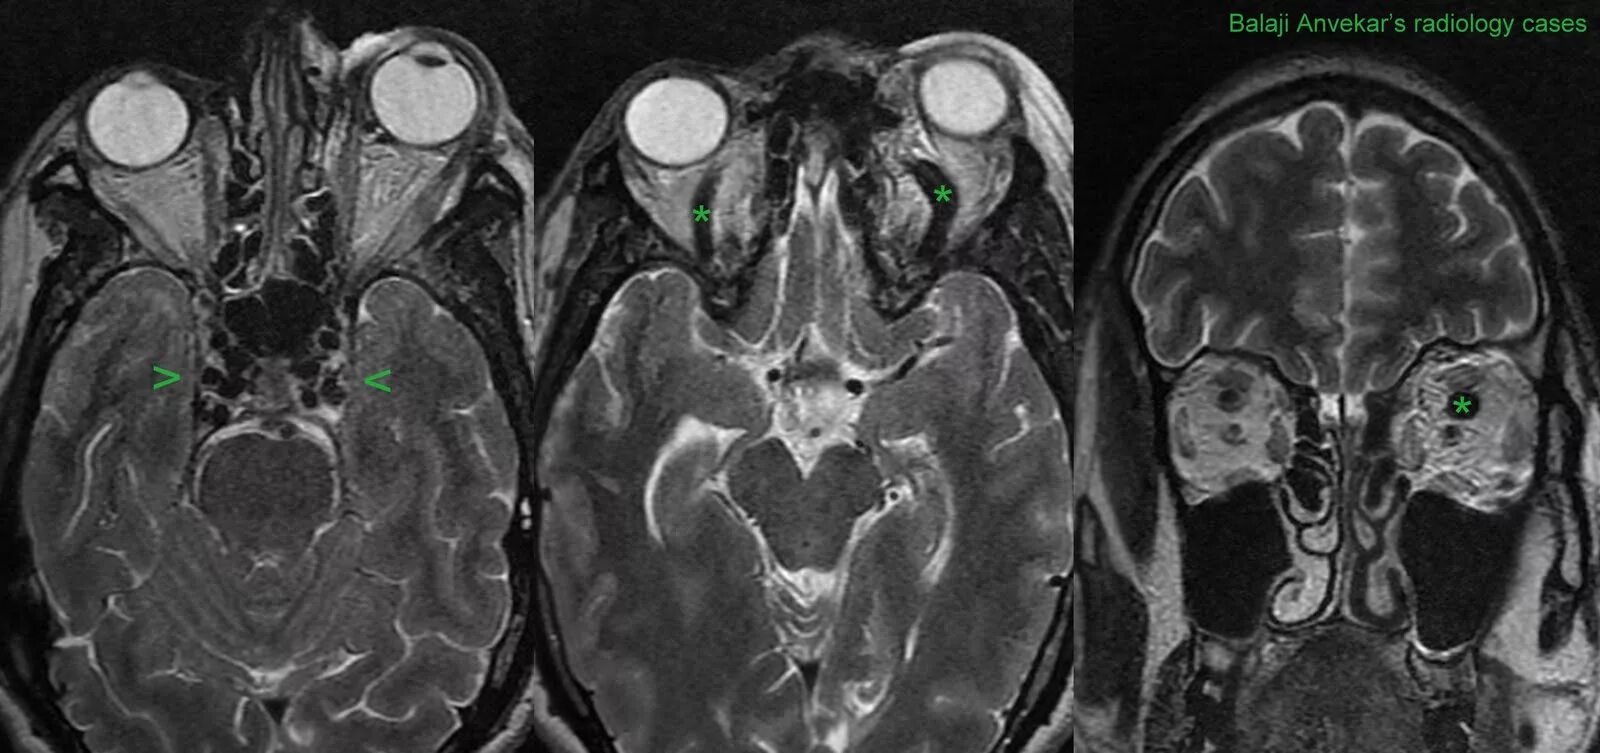

Тромбоз кавернозных